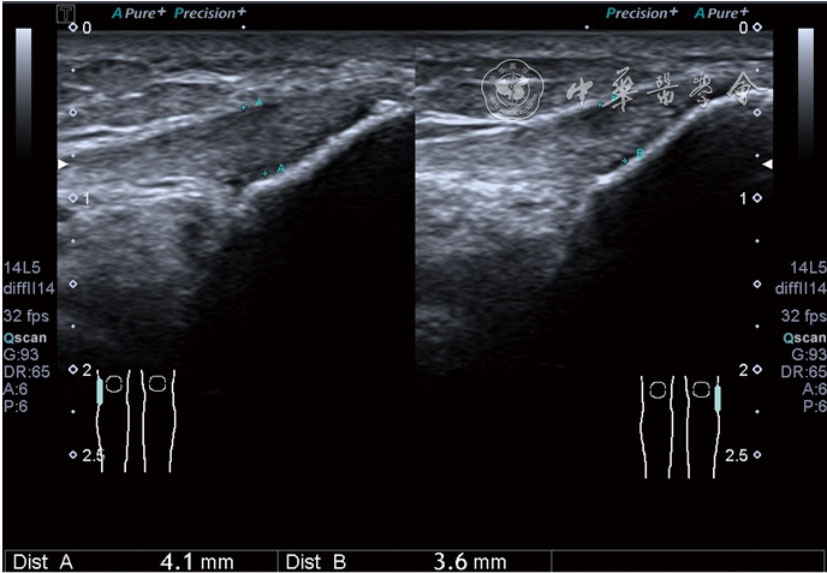

2.膝关节静态结构治疗。动力平衡失调后,继发静态结构变化,出现内外侧副韧带、交叉韧带、脂肪垫、半月板等结构变化。这里介绍半月板与交叉韧带的处理。(1)膝关节静态结构半月板治疗。在膝关节骨关节炎中主要是突出和损伤。突出主要发生于膝内翻引起的内侧半月板突出,引起内侧副韧带的张力增高。内侧半月板与内侧副韧带相连,是引起膝关节内侧疼痛的主要原因之一。治疗主要是针刀剥离松解,部分损伤可行PRP注射。①半月板突出针刀剥离松解治疗。针刀治疗主要是松解和减压,缓解疼痛,不能复位。以内侧半月板突出治疗为例。患者平卧位,髋轻度外展外旋,膝关节屈曲30°,膝下垫一软枕。选用10 MHz超声探头,穿刺区域常规消毒,探头涂抹耦合剂后套入无菌手套碘伏消毒或使用无菌耦合剂。将探头置于患者皮肤表面,内侧关节间隙长轴扫查,找到半月板突出最高点,用25G针头,抽吸1%利多卡因3 ml逐层麻醉直到半月板。选用直径1 mm的Ⅰ型2号针刀从头侧向足侧方向在内侧副韧带与半月板之间,以及半月板内部进行剥离松解3~5刀拔出针刀(图13),局部压迫5分钟,无菌敷料覆盖。②半月板损伤PRP注射治疗。半月板损伤主要表现为髌下痛,伸膝加重,查体在髌下髌韧带与侧副韧带之间,沿关节间隙有固定或局限性压痛,伸膝过程中尤为明显。MRI可示半月板断裂、损伤。如果出现绞索,严重影响功能需手术治疗。半月板损伤治疗,以注射PRP修复为主。以内侧半月板后角损伤为例。患者俯卧位,治疗前准备同半月板突出针刀剥离松解治疗。选用25G注射针头,抽取1%利多卡因2 ml局部麻醉后,制取1.5 ml PRP,穿刺到达半月板撕裂处注射,注射完毕后出针(图14),局部压迫2分钟,无菌敷料覆盖。(2)膝关节静态结构交叉韧带治疗。膝关节骨关节炎交叉韧带损伤多为部分损伤,治疗早期主要为药物或PRP注射,效果不佳时针刀做止点松解。①后交叉韧带损伤药物注射治疗。主要治疗韧带肿胀、无明显断裂患者。患者俯卧位,膝关节伸直位。一般选用10 MHz超声探头,治疗前准备同半月板突出针刀剥离松解治疗。将探头置于患者皮肤表面,后交叉韧带长轴扫查,找到胫骨止点,选用22G长针头,抽吸1%利多卡因3 ml+曲安奈德10 mg,从头侧向足侧方向穿刺到后交叉韧带胫骨止点部位的韧带表面进行注射,注射结束拔出针头(图15),局部压迫2分钟,无菌敷料覆盖。②前交叉韧带损伤PRP注射治疗。患者仰卧位,膝关节伸直。选用10 MHz超声探头,治疗前准备同半月板突出针刀剥离松解治疗。将探头置于患者皮肤表面,短轴扫查,找到前交叉韧带胫骨止点,选用25G针头,抽吸1%利多卡因3 ml逐层麻醉直到韧带止点部位,制备PRP 3 ml注射到前交叉韧带显露部位,注射结束拔出针头(图16),局部压迫2分钟,无菌敷料覆盖。③前交叉韧带损伤针刀剥离松解治疗。体位与治疗前准备同前交叉韧带损伤PRP注射治疗。短轴扫查找到前交叉韧带胫骨止点,选用25G针头,抽吸1%利多卡因3 ml逐层麻醉直到韧带止点部位,选用直径0.6 mm的Ⅰ型2号针刀从外侧向内侧于前交叉韧带胫骨止点部位剥离松解3~5刀拔出针刀(图17),局部压迫5分钟,无菌敷料覆盖。

图13 超声引导下半月板突出针刀剥离松解治疗